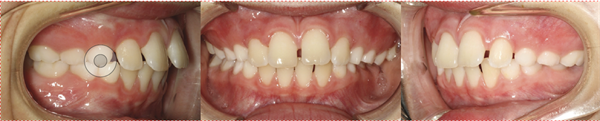

Fig. 3: Initial occlusal views (maxillary and mandibular) showing mild upper spacing and the constricted, lingually displaced lower left posterior segment.

The panoramic radiograph revealed mixed dentition appropriate for the patient’s age, with developing permanent dentition in normal eruption sequence. No pathology was identified (Fig. 4).

Fig. 4: Initial panoramic radiograph and lateral cephalogram confirming mixed dentition, Class I skeletal pattern, and normal root development.